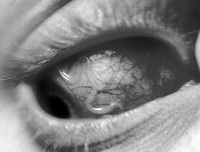

Скажем несколько слов о последствиях инфекции. Токсокароз, лечение которого началось слишком поздно, приводит к травмированию тканей, геморрагиям, некрозам, воспалительным изменениям. При поражении глазного нерва возможно развитие односторонней слепоты. Кроме того, токсокароз нередко провоцирует образование многочисленных гранулем в жизненно важных органах и системах.

При лечении токсокароза препаратами выбора являются тиабендазол, мебендазол и медамин. Они достаточно эффективны с точки зрения уничтожения мигрирующих особей, но практически не затрагивают личинок, которые находятся в гранулемах внутренних органов. С последними борется альбендазол, однако, этот препарат обладает сильным гепатотоксическим действием и потому его можно принимать только после консультаций с лечащим врачом. Глазной токсокароз у детей и взрослых лечат с помощью субконъюнктивальных инъекций депомедрола. В ряде случаев специалисты выносят решение о необходимости хирургического вмешательства.